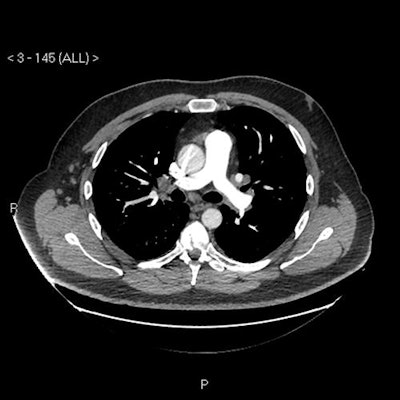

Imaging findings

"Our patient's CXR [chest x-ray] report was initially reported as normal (although we disagreed)," the authors wrote. "He subsequently had a CT pulmonary angiogram with high-resolution reconstruction (to exclude pulmonary thromboembolic as well as interstitial lung disease), reported as showing a ground glass, mosaic pattern in both lungs, with borderline enlarged hilar nodes, presumed reactive."